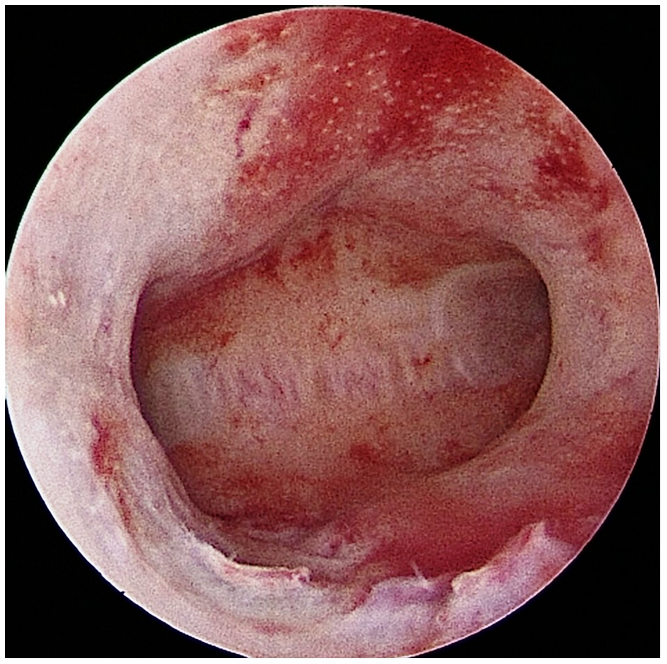

A hysteroscopy is a procedure that allows your doctor to look inside your uterus (womb) to diagnose and treat causes of abnormal bleeding or fertility issues. We use a hysteroscope-a thin, lighted telescope-like instrument. It is inserted through the vagina and cervix into the uterus. Because it enters through natural pathways, there are no cuts or incisions on your skin.

1. Diagnostic Hysteroscopy: Used to simply “look” and diagnose problems like polyps, fibroids, or structural issues.

● Adhesions (Asherman’s Syndrome): To remove scar tissue inside the uterus that can cause absent periods and infertility.

4. We release a fluid (usually saline) to expand the uterus, giving us a clear view of the lining and the openings of the fallopian tubes.